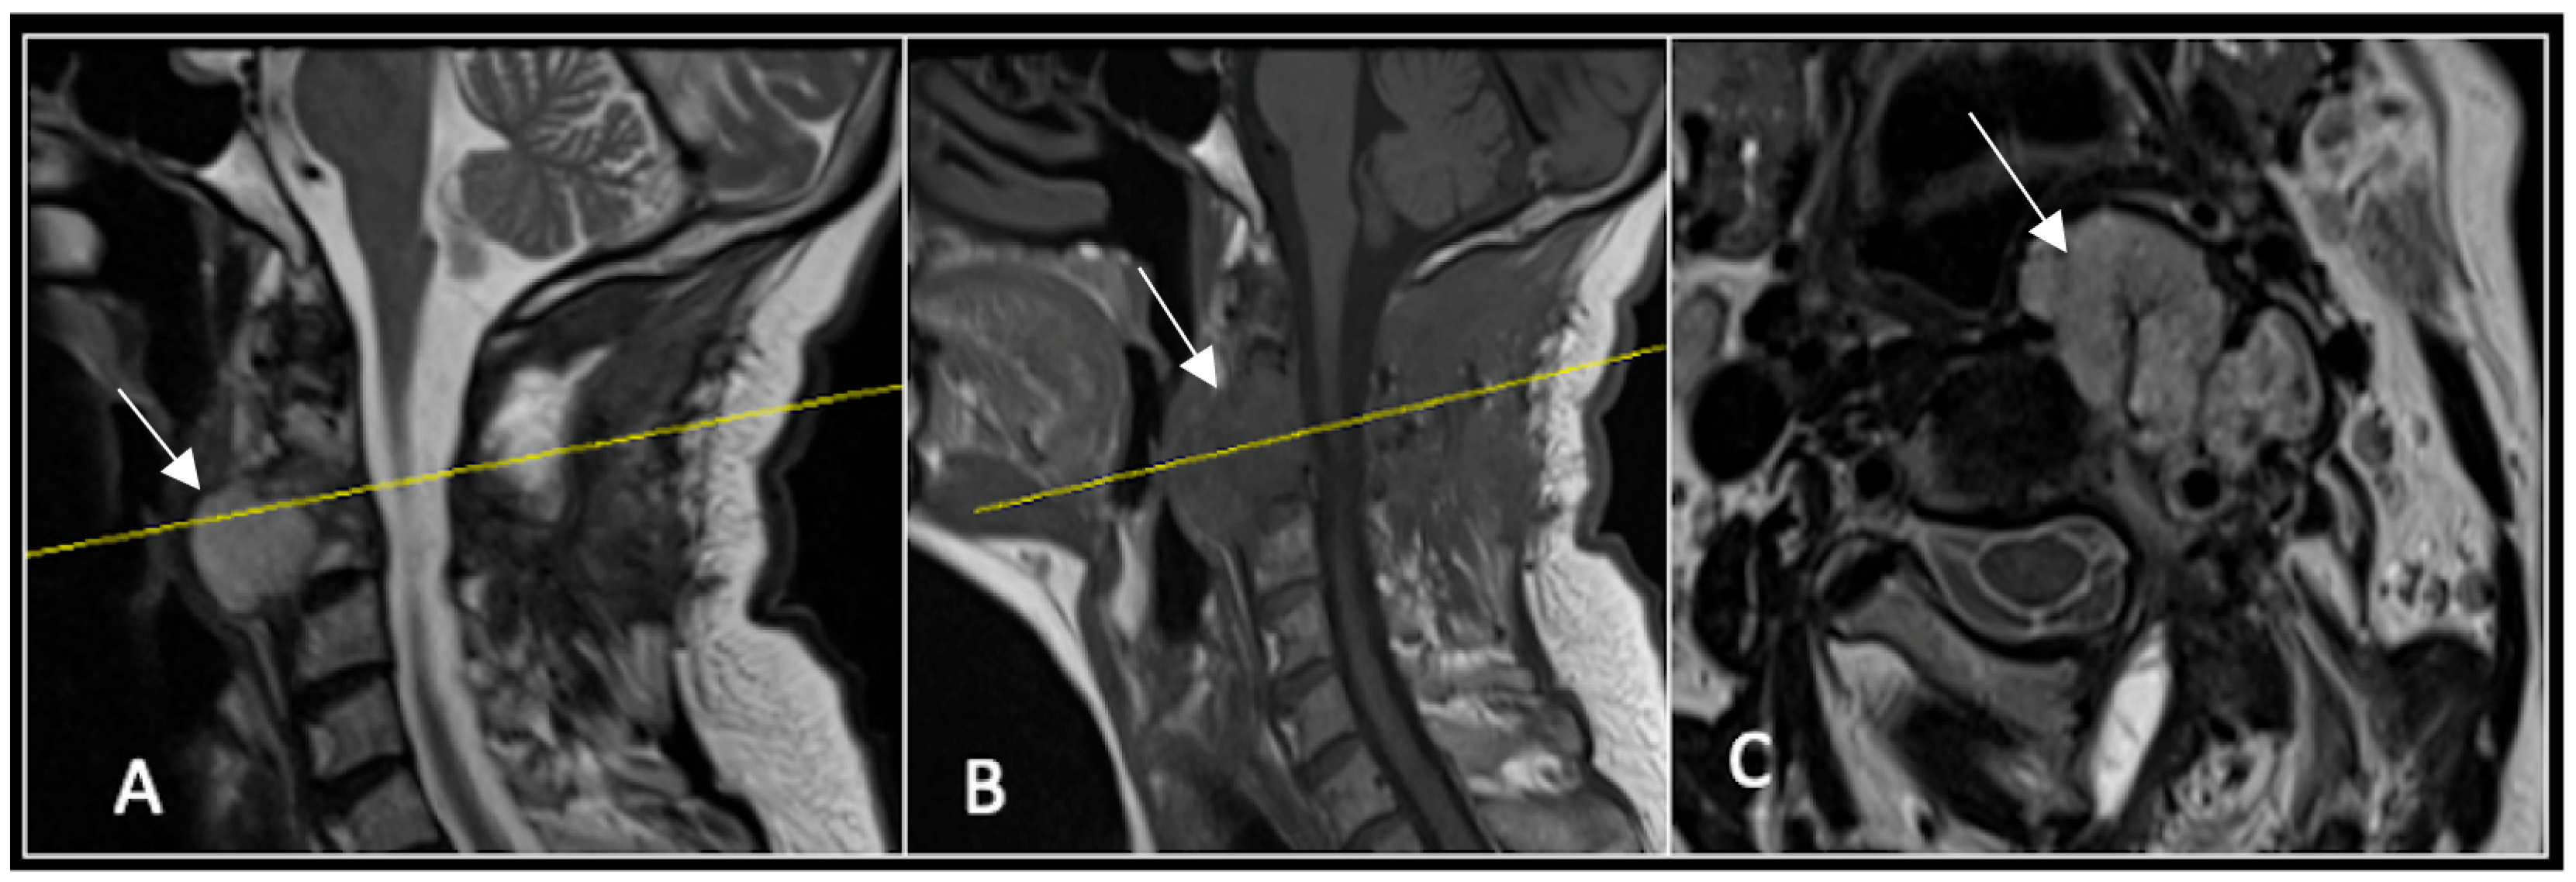

A 73-year-old male presented with an eight-month history of neck pain that was exacerbated on lying flat. He denied any symptoms of myelopathy and radiculopathy. He did not have any constitutional symptoms of malignancy. Past medical history included hypertension, renal cysts, and an ascending thoracic aneurysm. Examination was unremarkable. Diagnostic whole-spine MRI imaging demonstrated a large lobular mass localised to the cervical spine (Figure 2). Biopsy confirmed a conventional chordoma, and he underwent separation surgery followed by adjuvant proton beam therapy. Postoperative surveillance imaging at 12 months demonstrated stable disease (Figure 3).

Figure 3.

RI post-separation surgery showing reduction in tumour (arrow) dimensions and circumferential decompression. The posterior elements have been removed, and a posterior occipitocervical stablilsation has been performed. En-bloc resection would have necessitated sacrificing the left C2 nerve root and vertebral artery. The yellow line on the sagittal images indicates the level of the corresponding axial section. (A) T2W sagittal; (B) T1W sagittal; (C) T2-W axial.